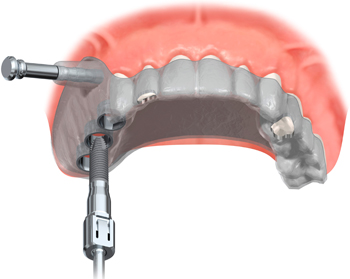

ノーベルガイド(NobelGuide)は、プロセラ・ソフトウェアを利用し、インプラントの治療計画から埋入までの一連の歯科インプラント治療をより安全で正確に行うための臨床応用システムです。

患者さんのCTスキャンデータをもとに、非常に精度の高いサージカルテンプレートが作製でき、より安全性に優れたインプラント埋入を可能にします。

このサージカルテンプレートとノーベルガイド専用外科キットを使用したガイディッド・サージェリーは、低侵襲のフラップレス術式を可能にし、患者負担を軽減します。また、事前に補綴物を作製することができるため、患者さんはインプラントを埋入した日に新しく機能する歯を手に入れることができます。

ガイデットサージェリーとは、CTの情報をもとにコンピューター3Dシミュレーション(ノーベルガイド)を行い、手術用のテンプレート(サージカルテンプレート)を装着し手術することです。

これにより、より安全に確実なインプラント治療を行うことができます。

また、ピンポイントでベストな位置にインプラントを埋入することが可能となりますので、より患者負担の少ない低侵襲治療には欠かせないシステムです。